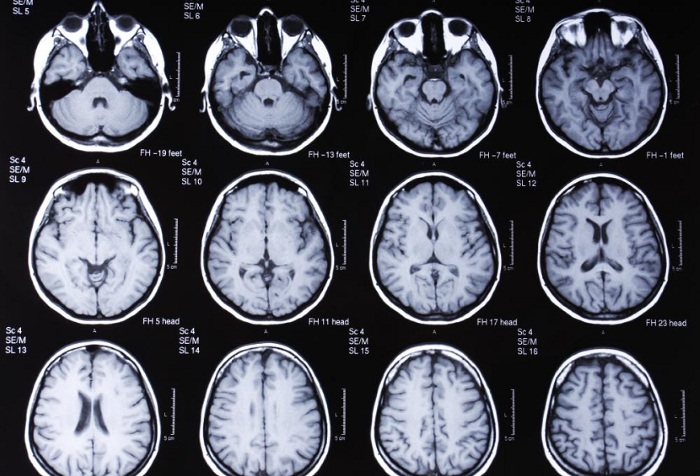

- КТ головы. Компьютерная томография позволяет получить послойную картинку, на которой можно более детально определить состояние головного мозга и кровеносных сосудов. Метод дает возможность выявить инородные элементы, опухолевые образования, травматические участки, воспаления оболочек, гематомы, кровоизлияния.

- МРТ головы. Метод дает объемное изображение головного мозга, все его структуры и ткани отображаются на мониторе в трехкратном измерении.